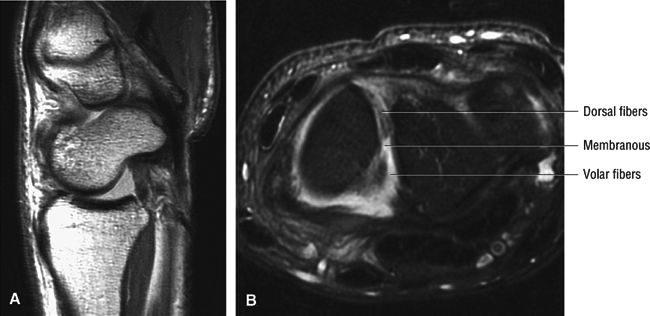

FIGURE 10.34 SCAPHOLUNATE LIGAMENT.

The scapholunate ligament is triangular on coronal section and is peripherally attached at the scapholunate interval. The inner apex of the triangular ligament is not attached to bone and is free within the scapholunate joint (Fig. 10.74).52

The dorsal fibers of the scapholunate ligament are oriented transversely, or perpendicular to the joint, and form a thick bundle. The dorsal portion of the scapho-lunate ligament is considered to be the most important component in maintaining carpal stability.

The membranous scapholunate ligament fibers course peripherally and obliquely from the scaphoid downward to the lunate. The membranous scapholunate ligament fibers attach to both bone and articular cartilage, whereas the dorsal and volar portions of the scapholunate ligament attach directly to bone.

The volar scapholunate ligament fibers course obliquely between the volar aspects of the lunate and scaphoid.

FIGURE 10.73 ● Anatomy of the scapholunate ligament complex on three separate coronal images. (A) Volar component. (B) Membranous component. (C) Dorsal component. (D) On a corresponding axial image all three components of the scapholunate ligament complex are demonstrated. The dorsal scapholunate ligament is horizontally oriented and is perpendicular to the joint. The fibers of the membranous portion of the scapholunate ligament course peripherally and obliquely from the scaphoid downward toward the lunate in a dorsal-to-volar direction. The volar scapholunate ligament courses obliquely from the scaphoid downward to the lunate. This arrangement of scapholunate ligament fibers biomechanically hinges the joint dorsally at the level of the dorsal transverse fibers. In forced extension, scapholunate ligament failure initiates in its volar aspect. S, scaphoid; L, lunate; v, volar component; m, membranous component; d, dorsal component. Arrows correspond to the course of each component of the scapholunate ligament.